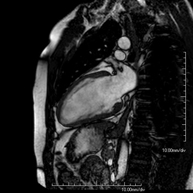

És una prova diagnòstica no invasiva que obté informació morfològica i funcional del cor i les estructures adjacents. D'aquesta manera es poden diagnosticar diferents patologies congènites i adquirides, o bé realitzar controls en pacients amb patologia prèvia ja coneguda. En la gran majoria de casos és necessari l'ús de contrast intravenós (Gadolini) per completar l'estudi, un tipus de contrast que rarament produeix reaccions adverses. Durant la prova el tècnic li demanarà diverses vegades que aguanti la respiració durant 10-15 segons per obtenir les imatges tant clares sigui possible. No es necessita preparació prèvia per part del pacient. La durada de la prova és de 45 – 60 aproximadament. Està contraindicada en pacients amb marcapassos. El pacient haurà d'avisar en cas que porti implants metàl·lics i/o clips quirúrgics. - RM cardíaca amb estrès miocardi

És una prova diagnòstica no invasiva que obté informació morfològica i funcional del cor i les estructures adjacents. D'aquesta manera es poden diagnosticar diferents patologies congènites i adquirides i realitzar controls en pacients amb patologia prèvia ja coneguda. En la majoria de casos és necessari l'ús de contrast intravenós (Gadolini) per completar l'estudi, un tipus de contrast que estranyament produeix reaccions adverses. Durant la prova el tècnic li demanarà diverses vegades que aguanti la respiració durant 10-15 segons per obtenir les imatges el més clares possible. No requereix preparació prèvia per part del pacient. La durada de la prova és d'aproximadament 45-60 minuts. Està contraindicada en pacients amb marcapassos i el pacient ha d'indicar si és portador d'implants metàl·lics i/o clips quirúrgics. - RM Cardíaca amb estrès miocàrdic